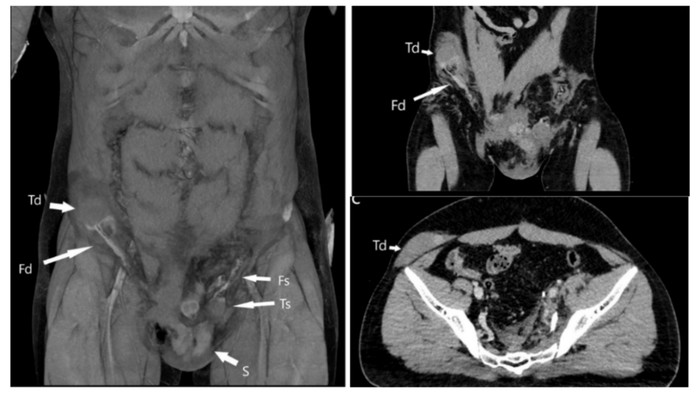

Lebih lanjut, dokter melakukan CT scan untuk menemukan lokasi testis yang telah berpindah tempat. Hasilnya, testisnya berpindah tempat jauh ke perut kanannya.

Pria yang tak disebutkan identitasnya itu awalnya mengalami kecelakaan motor. Hal itu membuat gonad atau kelenjar endokrin keluar dari skrotum dan melewati kanalis inguinalis, yaitu saluran kecil di selangkangan. Sampai akhirnya menetap di perut.

Dokter kemudian melakukan penanganan dengan menghangatkan testis yang kekurangan oksigen itu. Juga, mulai mengembalikan organ tersebut ke dalam soketnya melalui prosedur orkidopeksi, prosedur yang sering digunakan untuk merawat anak-anak yang buah zakarnya tidak turun sepenuhnya selama masa perkembangan.